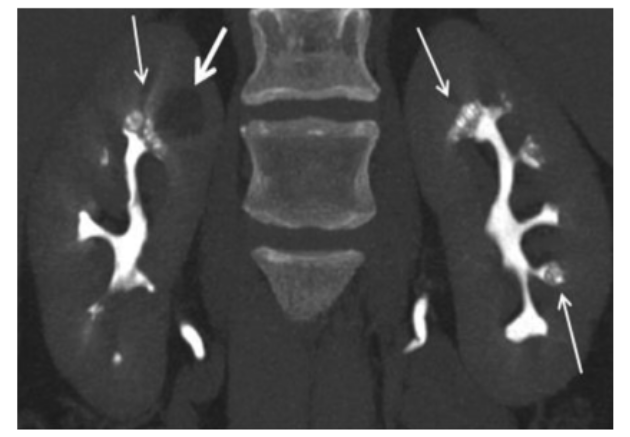

3.CT:①平扫期:乳头区及髓质密集簇状的小结石。②增强(排泄)期:显示扩张的集合管呈“囊状/葡萄串样”或 “花瓣征”,内部多有散在结石填充。

图4 MSK结石的增强CT排泄期相,可见囊状扩张的集合管被造影剂填充后出现“灯刷样"或"花束样"改变。